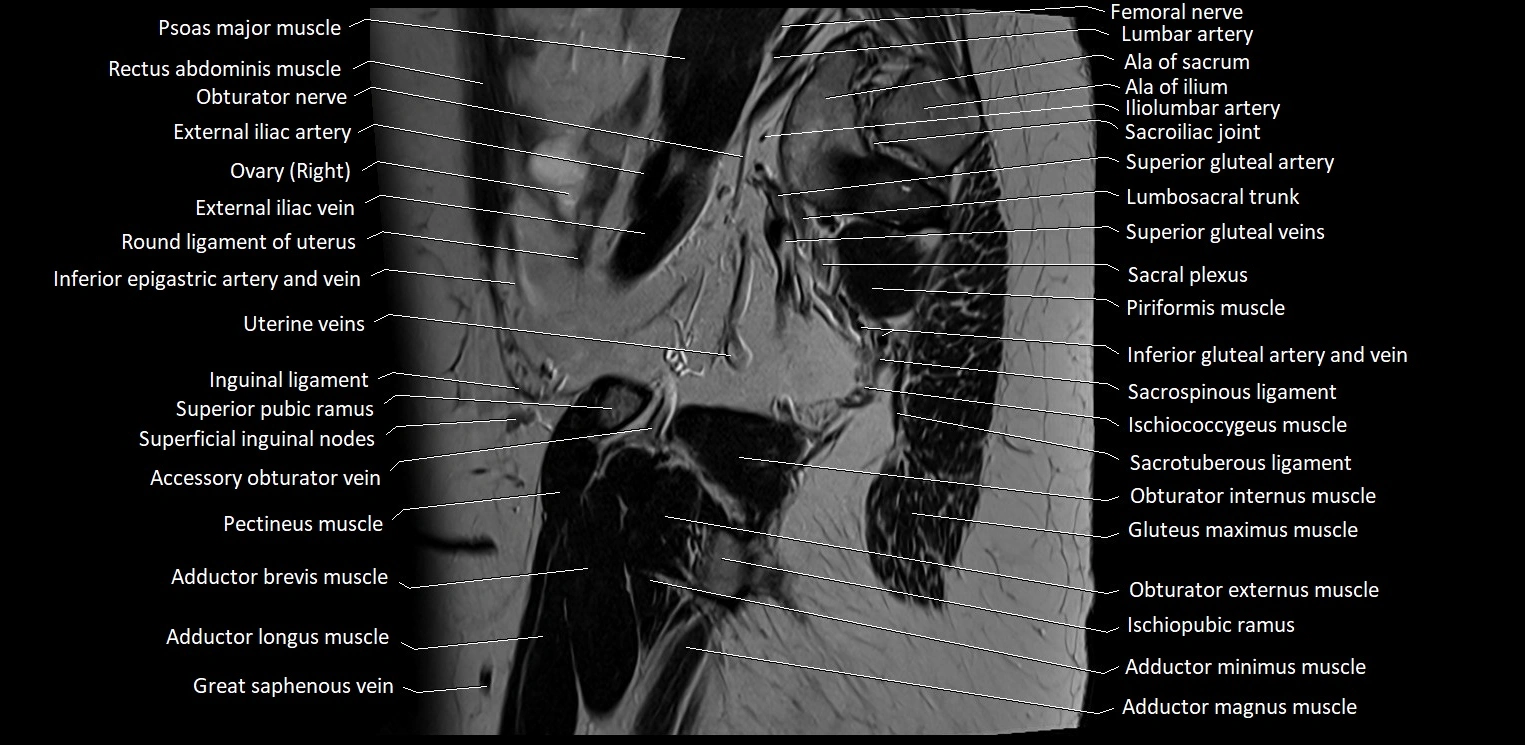

- Ala of ilium (wing of ilium)

- Ala of sacrum

- External iliac artery

- External iliac vein

- Femoral nerve

- Lumbosacral trunk

- Obturator nerve

- Pectineus muscle

- Piriformis muscle

- Right ovary

- Round ligament of uterus

- Sacral plexus

- Sacrospinous ligament

- Sacrotuberous ligament

- Sartorius muscle

- Superficial inguinal lymph nodes

- Superior gluteal artery

- Superior gluteal veins

- Uterine veins